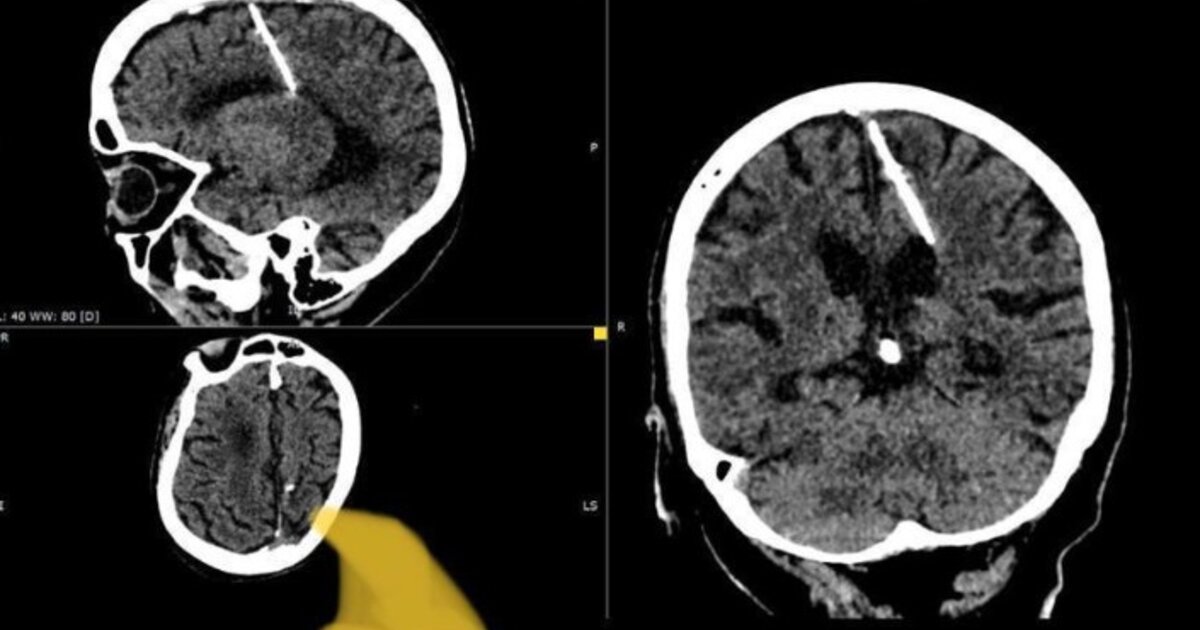

Έζησε όλη της τη ζωή με μια βελόνα στον εγκέφαλο!

Η βελόνα ανακαλύφθηκε όταν η γυναίκα υποβλήθηκε σε αξονική τομογραφία - Πιθανότατα ήταν απόδειξη της κακής προσπάθειας των γονιών της 80χρονης να τη σκοτώσουν ενώ ήταν ακόμη βρέφος κατά τη διάρκεια του Β’ Παγκοσμίου Πολέμου

Γιατροί στη Ρωσία ανακάλυψαν πως μία ηλικιωμένη έχει ζήσει σχεδόν ολόκληρη τη ζωή της με μία βελόνα σφηνωμένη στον εγκέφαλό της.

Οι γιατροί στο απομακρυσμένο ρωσικό νησί Σαχαλίνη στον Ειρηνικό Ωκεανό κατέληξαν στο συμπέρασμα ότι η βελόνα πιθανότατα ήταν απόδειξη της κακής προσπάθειας των γονιών της 80χρονης να τη σκοτώσουν ενώ ήταν ακόμη βρέφος κατά τη διάρκεια του Β’ Παγκοσμίου Πολέμου.

Στην περίπτωση της ηλικιωμένης ασθενούς, η βελόνα μήκους 1,2 ιντσών τρύπησε τον αριστερό βρεγματικό λοβό της, αλλά αυτό «δεν οδήγησε στο επιδιωκόμενο αποτέλεσμα», σημείωσαν οι αρμόδιοι στο υπουργείο.

Το αιχμηρό αντικείμενο ανακαλύφθηκε φέτος όταν η 80χρονη πήγε σε κλινική για να υποβληθεί σε αξονική τομογραφία. Οι γιατροί αποφάσισαν να μην αφαιρέσουν την βελόνα φοβούμενοι ότι μπορεί να βλάψει τον εγκέφαλό της.